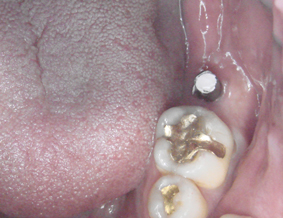

DSC01671.JPG

前回につけたインプラントの

青いキャップを外します

前回にキャップをつけないで

歯肉で覆い被せた場合は

麻酔をして歯肉に穴開けします

痛いというほどではないです